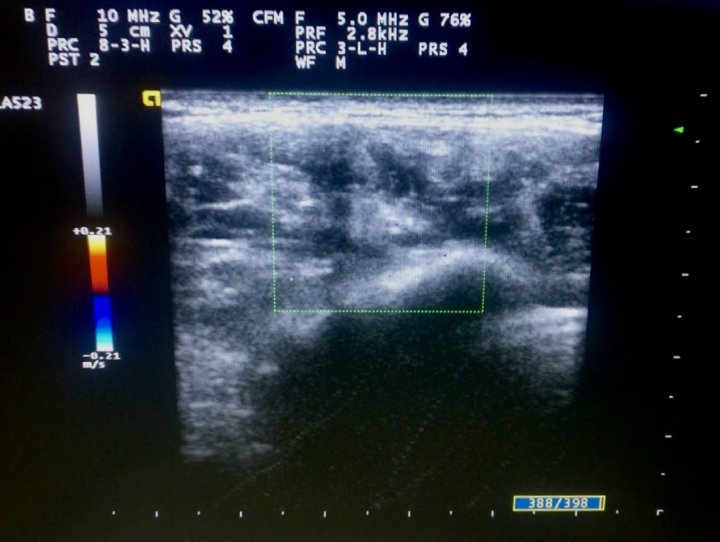

Combined vascular malformation affecting the facial region is an extremely rare clinical entity that is debilitating both functionally and emotionally. Treatment warrants a multidisciplinary approach with the aim of removing the vascular anomalies and ameliorating any functional facial disfigurement. Here, we present a case of a 40-year-old female with combined vascular malformation of the face who was treated successfully with surgical intervention accompanying significant resolution of facial disfigurement.

Abstract Image